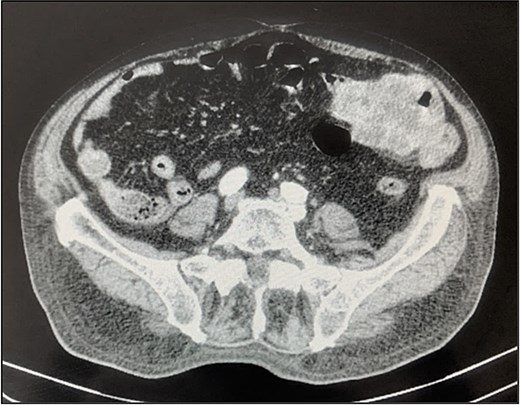

A contrast-enhanced chest-abdominal-pelvic computed tomography (CT) scan revealed a solid, multilobular mass, with approximately 8 × 6 × 8 cm, likely originating from the SB, with asymmetric wall thickening, heterogeneous contrast enhancement, areas consistent with necrosis and central calcification (Figs 1 and 2), suggestive of GIST. Simultaneously, a solid nodular lesion was identified on the anterior wall of the rectum, exhibiting exophytic growth with a heterogeneous texture, well-defined borders and measuring 5 × 3 cm, without adjacent fat infiltration, raising suspicion of another GIST (Fig. 3).